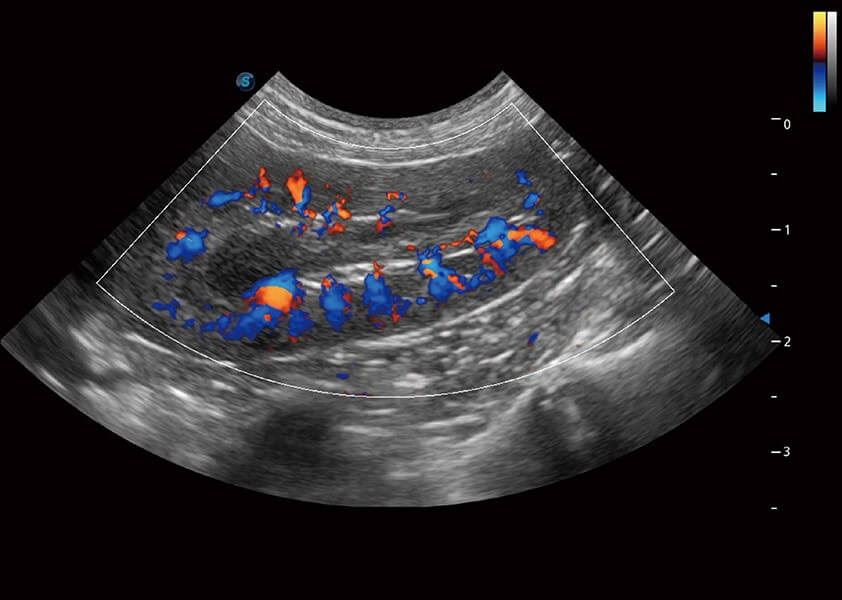

ProPet 60 作为一款高端台式动物超声设备,为动物医生的日常诊断提供了一系列贴合动物临床需求、解决临床实际问题的高级成像功能。凭借全系列高清探头,满足医生对腹部、心脏、生殖、浅表、肌骨等成像的所有需求,切实帮助您提升检查效率,提高诊断信心。

ProPet 60 尊享版

兽用彩色多普勒超声诊断系统